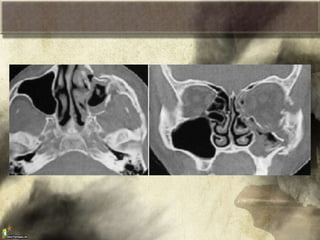

Fracturas Nasales

• Son las mas comunes

• Afecta huesos, cartílago y tabique

• Dos patrones:

– Lateral: desplaza y fractura al tabique

– De frente: aplastamiento de la nariz,

ensanchamiento superior, gran daño al tabique

• Diagnostico es clinico, dolor, epistaxis,

laterorrinia, aplastamiento, obstruccion nasal,

espiculas oseas

• *Rx para corroborar la fractura del

tratamiento.

Siempre inspeccionar mediante especuloscopia

anterior el septo para buscar hematomas

septales, hay riesgo de necrosis de infección

• Proyeccion de waters para valorar el tabique

Fracturas naso-orbito-etmoidal

• Fractura que involucra el etmoides, la rama

ascendente del maxilar superior y los huesos

nasales propios

• Hay signos de fractura de pared medial de la

orbita y de fractura nasal, pero con depresion

de la nariz.

Se clasifican en 3 tipos

– I central unico sin compromiso del telecanto

– II central conminuta sin compromiso del

telecanto

– III central conminuta con compromiso del